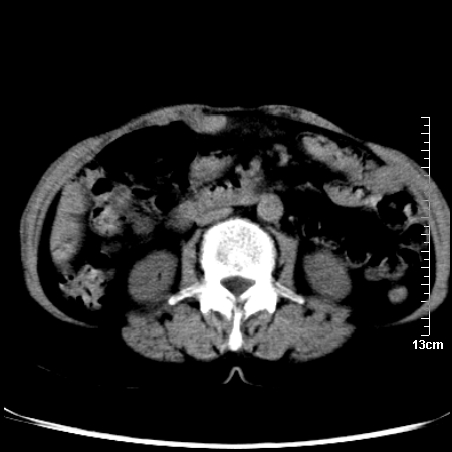

巨大囊实性包块,边界大部尚清楚,不太像脓肿的表现。应该做个增强检查除外盆腔肿瘤。

脓肿可能性大. 因回盲部区域化脓性兰尾切除残端感染改变征像与实性肿块关系密切.肿块上界至右下腹,下界至盆腔膀胱上缘, 如果是实性肿块在兰尾术中可能就会发现. 所以术后一周病人高烧, 白细胞增高,临床表现支持脓肿.

盆腔一边界大部份清晰囊实性肿块,其周腹脂未见确切异常,其一端与右侧附件相连。考虑右侧附件肿瘤。

因术前未做相关检查,故漏诊完全有可能!若脓肿这么大,临床不会单纯是阑尾炎的体征!支持:盆腔肿瘤——首选:附件来源的肿瘤,建议增强扫描!!!

实质性囊腺瘤可能